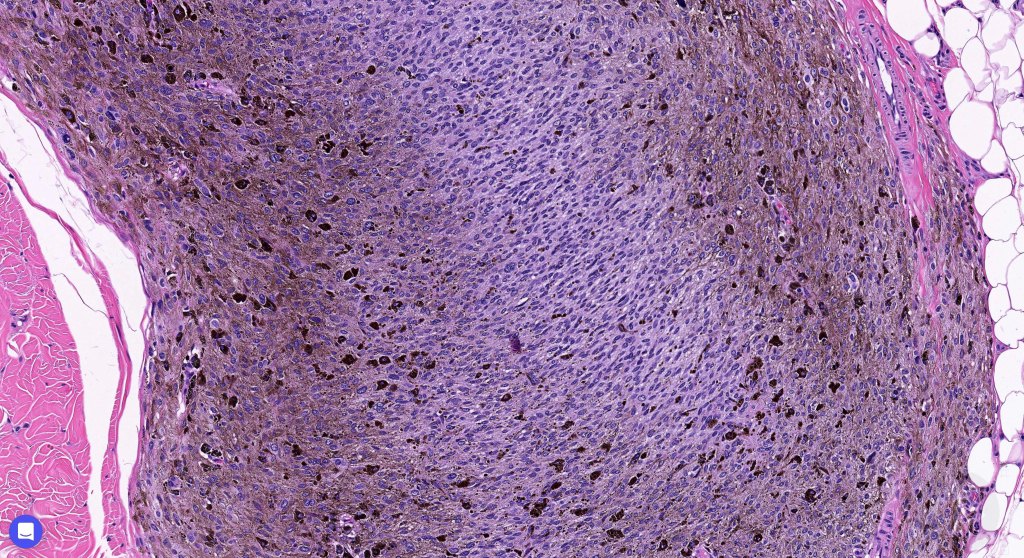

•Most characteristic is the dumbbell silhouette although a plague morphology may also be encountered

•Admixture of spindle cells, pigmented bipolar or dendritic cells & melanophages

•Cytoplasm is pale and nuclei are small with inconspicuous nucleoli

•An alveolar pattern is characteristic particularly with clear cell nodules

•Mitoses are typically very sparse or absent

•Stromal fibrosis, myxoid change, vascular hyalinization with cyst formation are often seen